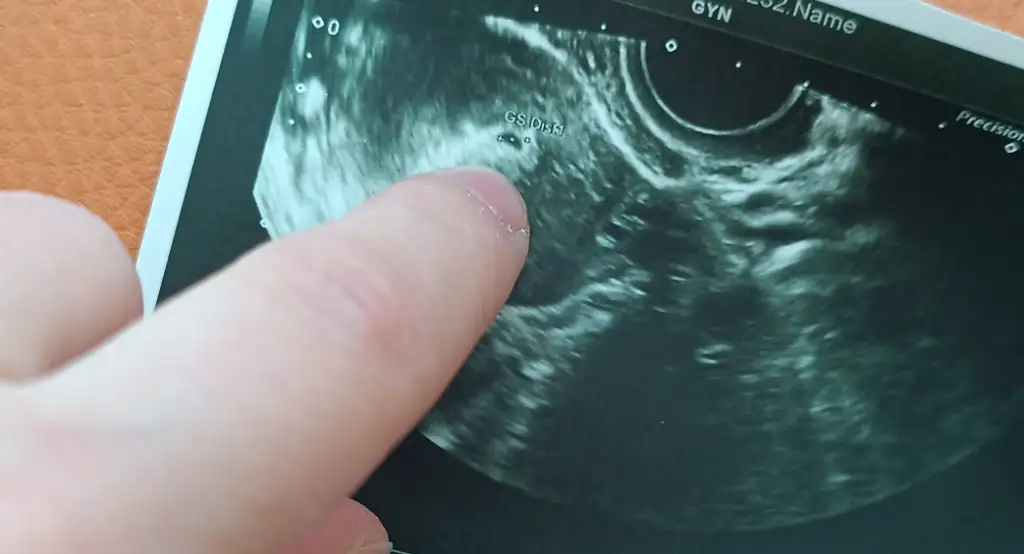

mujdebebe Üye Kayıtlı Üye 11 Nisan 2025 145 60 13 31 17 Haziran 2025 Konu Sahibi Konu Sahibi mujdebebe #21 DNurr .!.: Yorumlayabilecek birisi var mı acaba Genişletmek için tıkla... Benim buna keseyi gördük dedi doktor, seninki de sanki keseye benziyor Eklentiler IMG_20250617_165142.webp 20 KB · Görüntüleme: 50

DNurr .!.: Yorumlayabilecek birisi var mı acaba Genişletmek için tıkla... Benim buna keseyi gördük dedi doktor, seninki de sanki keseye benziyor